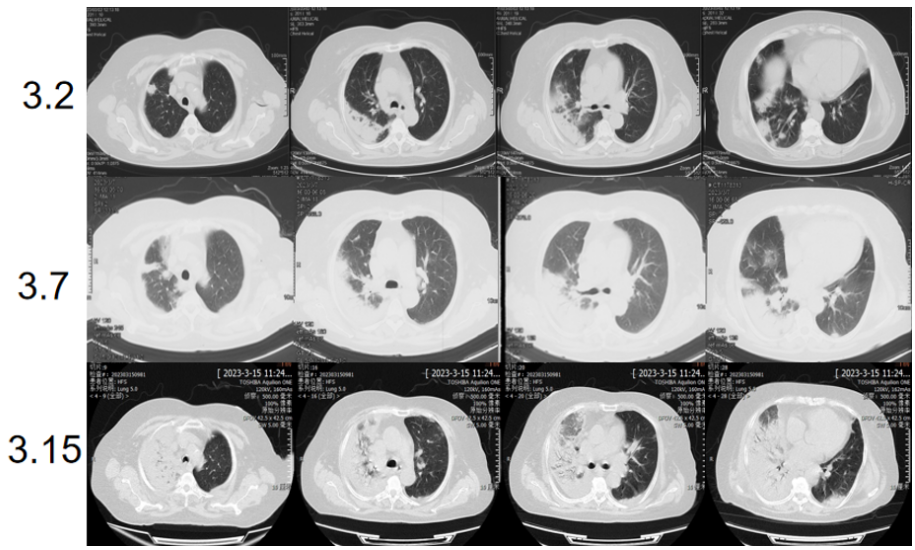

对于ARDS的治疗,目前证据级别较高的治疗手段主要是支持治疗。但对因治疗才是改善预后的根本。同时,一些疾病虽然影像学表现和病程变化符合ARDS的标准,但有特异性的病因。如果不能及时查明病因,会延误治疗时机。图1所示,胸片可见双肺多发渗出影,胸部CT可见以右肺为主的大片磨玻璃渗出,小叶间隔增厚。该患者病情迅速进展,胸片出现双肺弥漫渗出影。虽然病程及影像变化符合ARDS的特点。但经过外科肺活检和肺泡灌洗后,BALF细胞学可以发现吞噬大量磷脂蛋白的巨噬细胞, PAS染色阳性。同时,病理提示肺泡腔及小气道中大量PAS染色阳性的物质。该患者通过活检和细胞学诊断为肺泡蛋白沉积症(PAP)。图2胸片可见两侧弥漫渗出,BALF低倍镜下可见大量嗜酸细胞浸润,最终诊断为急性嗜酸细胞性肺炎。由此可见,ARDS的病因诊断极为重要。

图2  一例急性嗜酸性细胞性肺炎患者影像学及病理学表现